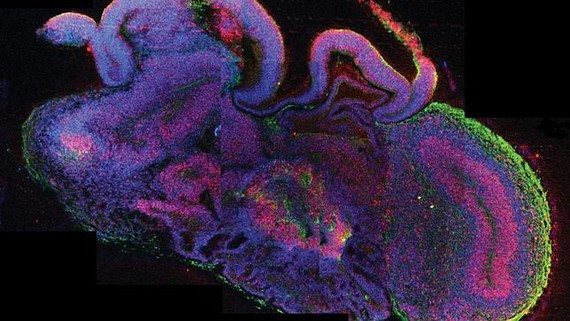

Un equipo internacional de investigadores, liderados por el austriaco Juergen Knoblich, ha logrado por primera vez obtener en el laboratorio pequeños cerebros del tamaño de un guisante que reflejan de forma bastante fiel las primeras etapas del desarrollo del cerebro humano. Este “fascinante” trabajo, como le califican varios científicos internacionales, ha dado ya su primer fruto: un minicerebro a partir de células madre pluripontentes inducidas (IPs) de un paciente con microcefalia, un grave trastorno del desarrollo que reduce el tamaño del cerebro, que han logrado corregir "in vitro" según publican en el último número de “Nature”.

Este “organoide cerebral”, como le denominan sus creadores, se ha obtenido a partir de un cultivo de tejido de células madre pluripotentes humanas que, lejos de reordenarse de forma caótica, se grupan formando una estructura esférica querecapitula en parte las primeras etapas de la organización del cerebro humano y en concreto de la corteza cerebral. Este trabajo puede ayudar a superar algunas de las limitaciones actuales del estudio de las enfermedades neurológicas utilizando modelos animales, como los ratones, que no comparten la complejidad del cerebro humano y han demostrado ser peores predictores del resultado posterior de los fármacos en pacientes humanos.

“El estudio es importante porque permite un modelo experimental interesante para estudiar el desarrollo de la corteza cerebral” explica Juan A. de Carlos Investigador del Instituto Cajal (CSIC) y experto en desarrollo del telencéfalo. De Carlos resalta que el equipo de Knoblich “ha logrado una peculiar estructura en cultivo, a partir de un puñado de células madre humanas, a las que han inducido para que se diferencien en células nerviosas. Estas estructuras, a las que denominan organoides cerebrales, se pueden mantener en cultivo durante meses, tiempo en el que crecen adoptando una forma mas o menos amorfa, pero que al estudiarla con distintos marcadores se observa que existe una microorganización coherente a lo largo del tiempo con la de la corteza cerebral humana en desarrollo”. De hecho las células se organizan en capas, igual que ocurre en la corteza cerebral, el tejido más complejo de todos.

Se observan importantes similitudes entre este organoide en proporción, organización y movimiento de las células que luego van a dar origen a los distintos tipos de neuronas. Además, algunas estructuras, como la pituitaria o el ojo pueden desarrollarse hasta una etapa relativamente avanzada con este método, lo que abre interesantes posibilidades en medicina regenerativa.